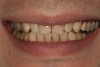

Fig 1. Preoperative smile photograph.

Figure 1

A 34-year-old male patient with no medical issues presented to the office with the chief complaint of a failing crown on tooth No. 12. The patient was also unhappy with his bite and the appearance of his teeth (Figure 1 and Figure 2).

The dentofacial examination revealed a low smile line with no incisor display when the lips were in repose. The anterior teeth were chipped and worn, and their overall color was darkened. The buccal corridors were deficient, and the failing crown on tooth No. 12 was visible in a full smile.